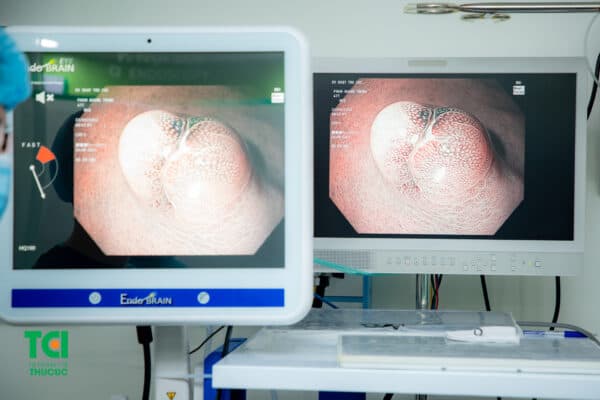

Nội soi phóng đại cho hình ảnh được phóng đại hàng trăm lần.

2.2. Nội soi dạ dày đại tràng nhuộm màu MCU tiên lượng tính chất tổn thương

Bác sĩ có thể trực tiếp nhuộm màu tại vùng tổn thương bằng chất chuyên dụng. Mỗi vị trí khác nhau, loại tổn thương sẽ được chỉ định loại chất nhuộm màu phù hợp tương ứng. Các chất nhuộm màu này đều được Bộ Y tế cấp phép, đảm bảo an toàn với đường tiêu hóa.

Việc nhuộm màu tổn thương sẽ giúp làm rõ cấu trúc vi bề mặt, xác định chính xác ranh giới tổn thương và đặc biệt thông qua hình ảnh nhuộm mà bác sĩ còn có thể tiên lượng tốt về tính chất tổn thương.